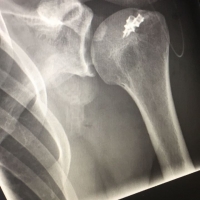

Was ist passiert ? Bereits Ende Februar bin ich sehr dynamisch aus einem Boulder gerauscht. Genau diese Dynamik sorgte leider dafür , dass die Füße eher zuletzt auf dem Boden einschlugen.

Im nachhinein hat sich herausgestellt, dass die Sehne bereits vorgeschädigt war und die umgebenden Muskeln in der Schulter die Funktion des Supraspinatus (einer der Muskeln in der sogenannten Rotatorenmanschette der Schulter) teilweise übernommen hatten. Dadurch hat der erstdiagnostizierende Arzt zunächst auch einen Riss im Muskel- oder Sehnenapparat für unwahrscheinlich gehalten. Nach der später richtig erstellten Diagnose folgte OP und mindestens bis Herbst Kletterpause.